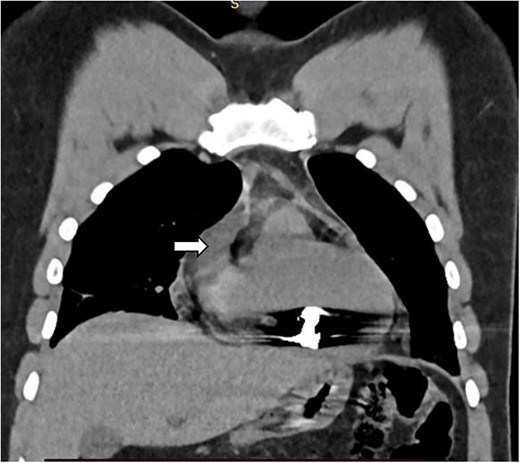

There was a healed scar on the undersurface of the right ventricular wall deep in the myocardium close to the septum and posterior descending artery. The scar was opened, the bullet was extracted along with minimal purulent discharge, which was drained, the cavity was irrigated, and the defect was closed using artificial membrane polytetrafluoroethylene (PTFE) (teflon). Patient was weaned off the CPBP and regular heart beat was achieved. And the patient was extubated on table and was transferred to the cardiac intensive care unit (CICU) with stable condition and normal vital signs. The postoperative course of the patient was uneventful and he stayed a total of 7 days in the hospital after surgery, with 2 days in the CICU and the remaining in the regular ward. He was administered cefepime and vancomycin because of the intraoperatively detected purulent pericardial discharge. His postoperative echocardiography detected normal myocardial activity with no wall motion abnormality and no pericardial effusion. He was discharged on the seventh postoperative day with a stable condition. He was followed as an outpatient and has improved (Figs 4 and 5).

Partially extruded bullet located within the right ventricle wall.